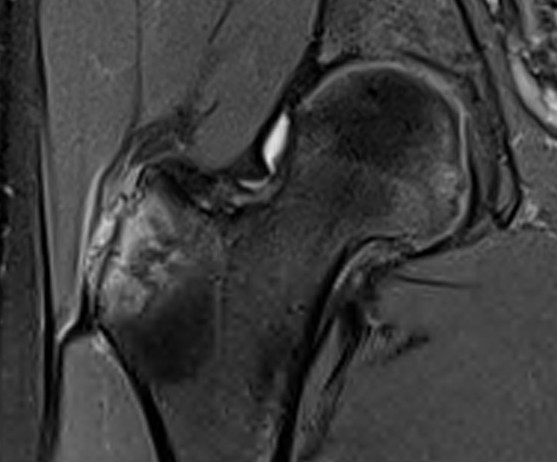

Intact gluteus medius insertion

Torn gluteus medius and minimus

Acute tear gluteus medius